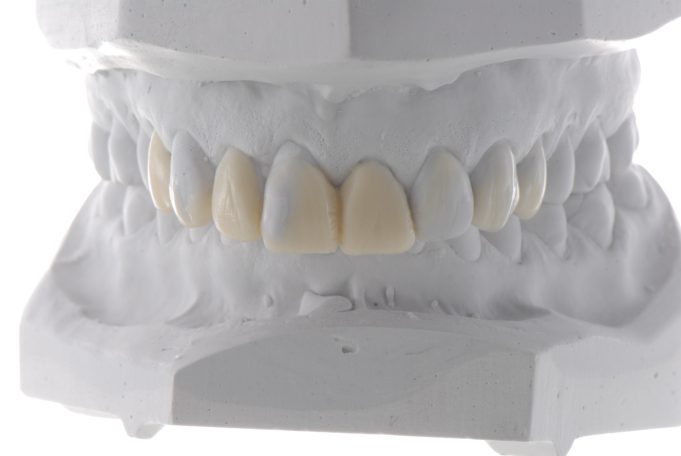

Metallfreie Frontzahnkronen mit individueller keramischer Verblendung.

Kombination aus vollkeramischen Frontzahnkronen und metallbasierten Seitenzahnkronen mit dünn auslaufenden Rändern.